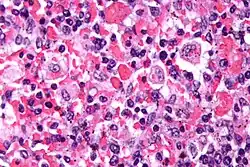

| Micrograph showing red blood cells within macrophages. H&E stain. | |